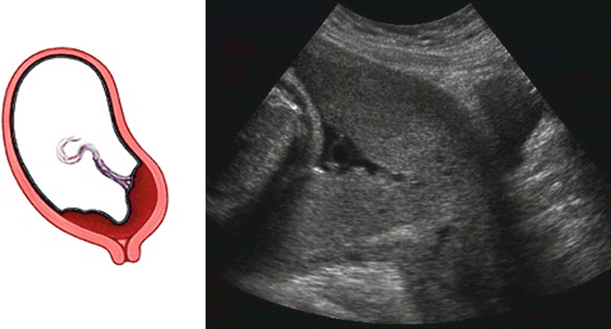

Placenta previa. Transabdominal sonography shows the cervix (lower ...

Spectrum of placenta previa. (a) Transvaginal US image obtained at ...

Transabdominal Ultrasound In Placenta Previa